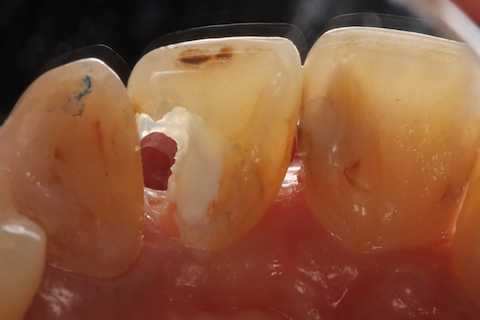

40代女性、右上2、自発痛-

かなりひどい虫歯で、外側表面のエナメル質はなんとか残したが、ペラペラだ。

スプーンエキスカベータで軟化象牙質を剥がすと簡単に露髄した(黄色矢印)。

ひどい虫歯ほど麻酔は要らない。健全な象牙質は削ったり、それどころかエアーを吹きかけたりするだけで痛いのだが、このような健全ではない象牙質は痛くない。露髄して出血しても痛くない。